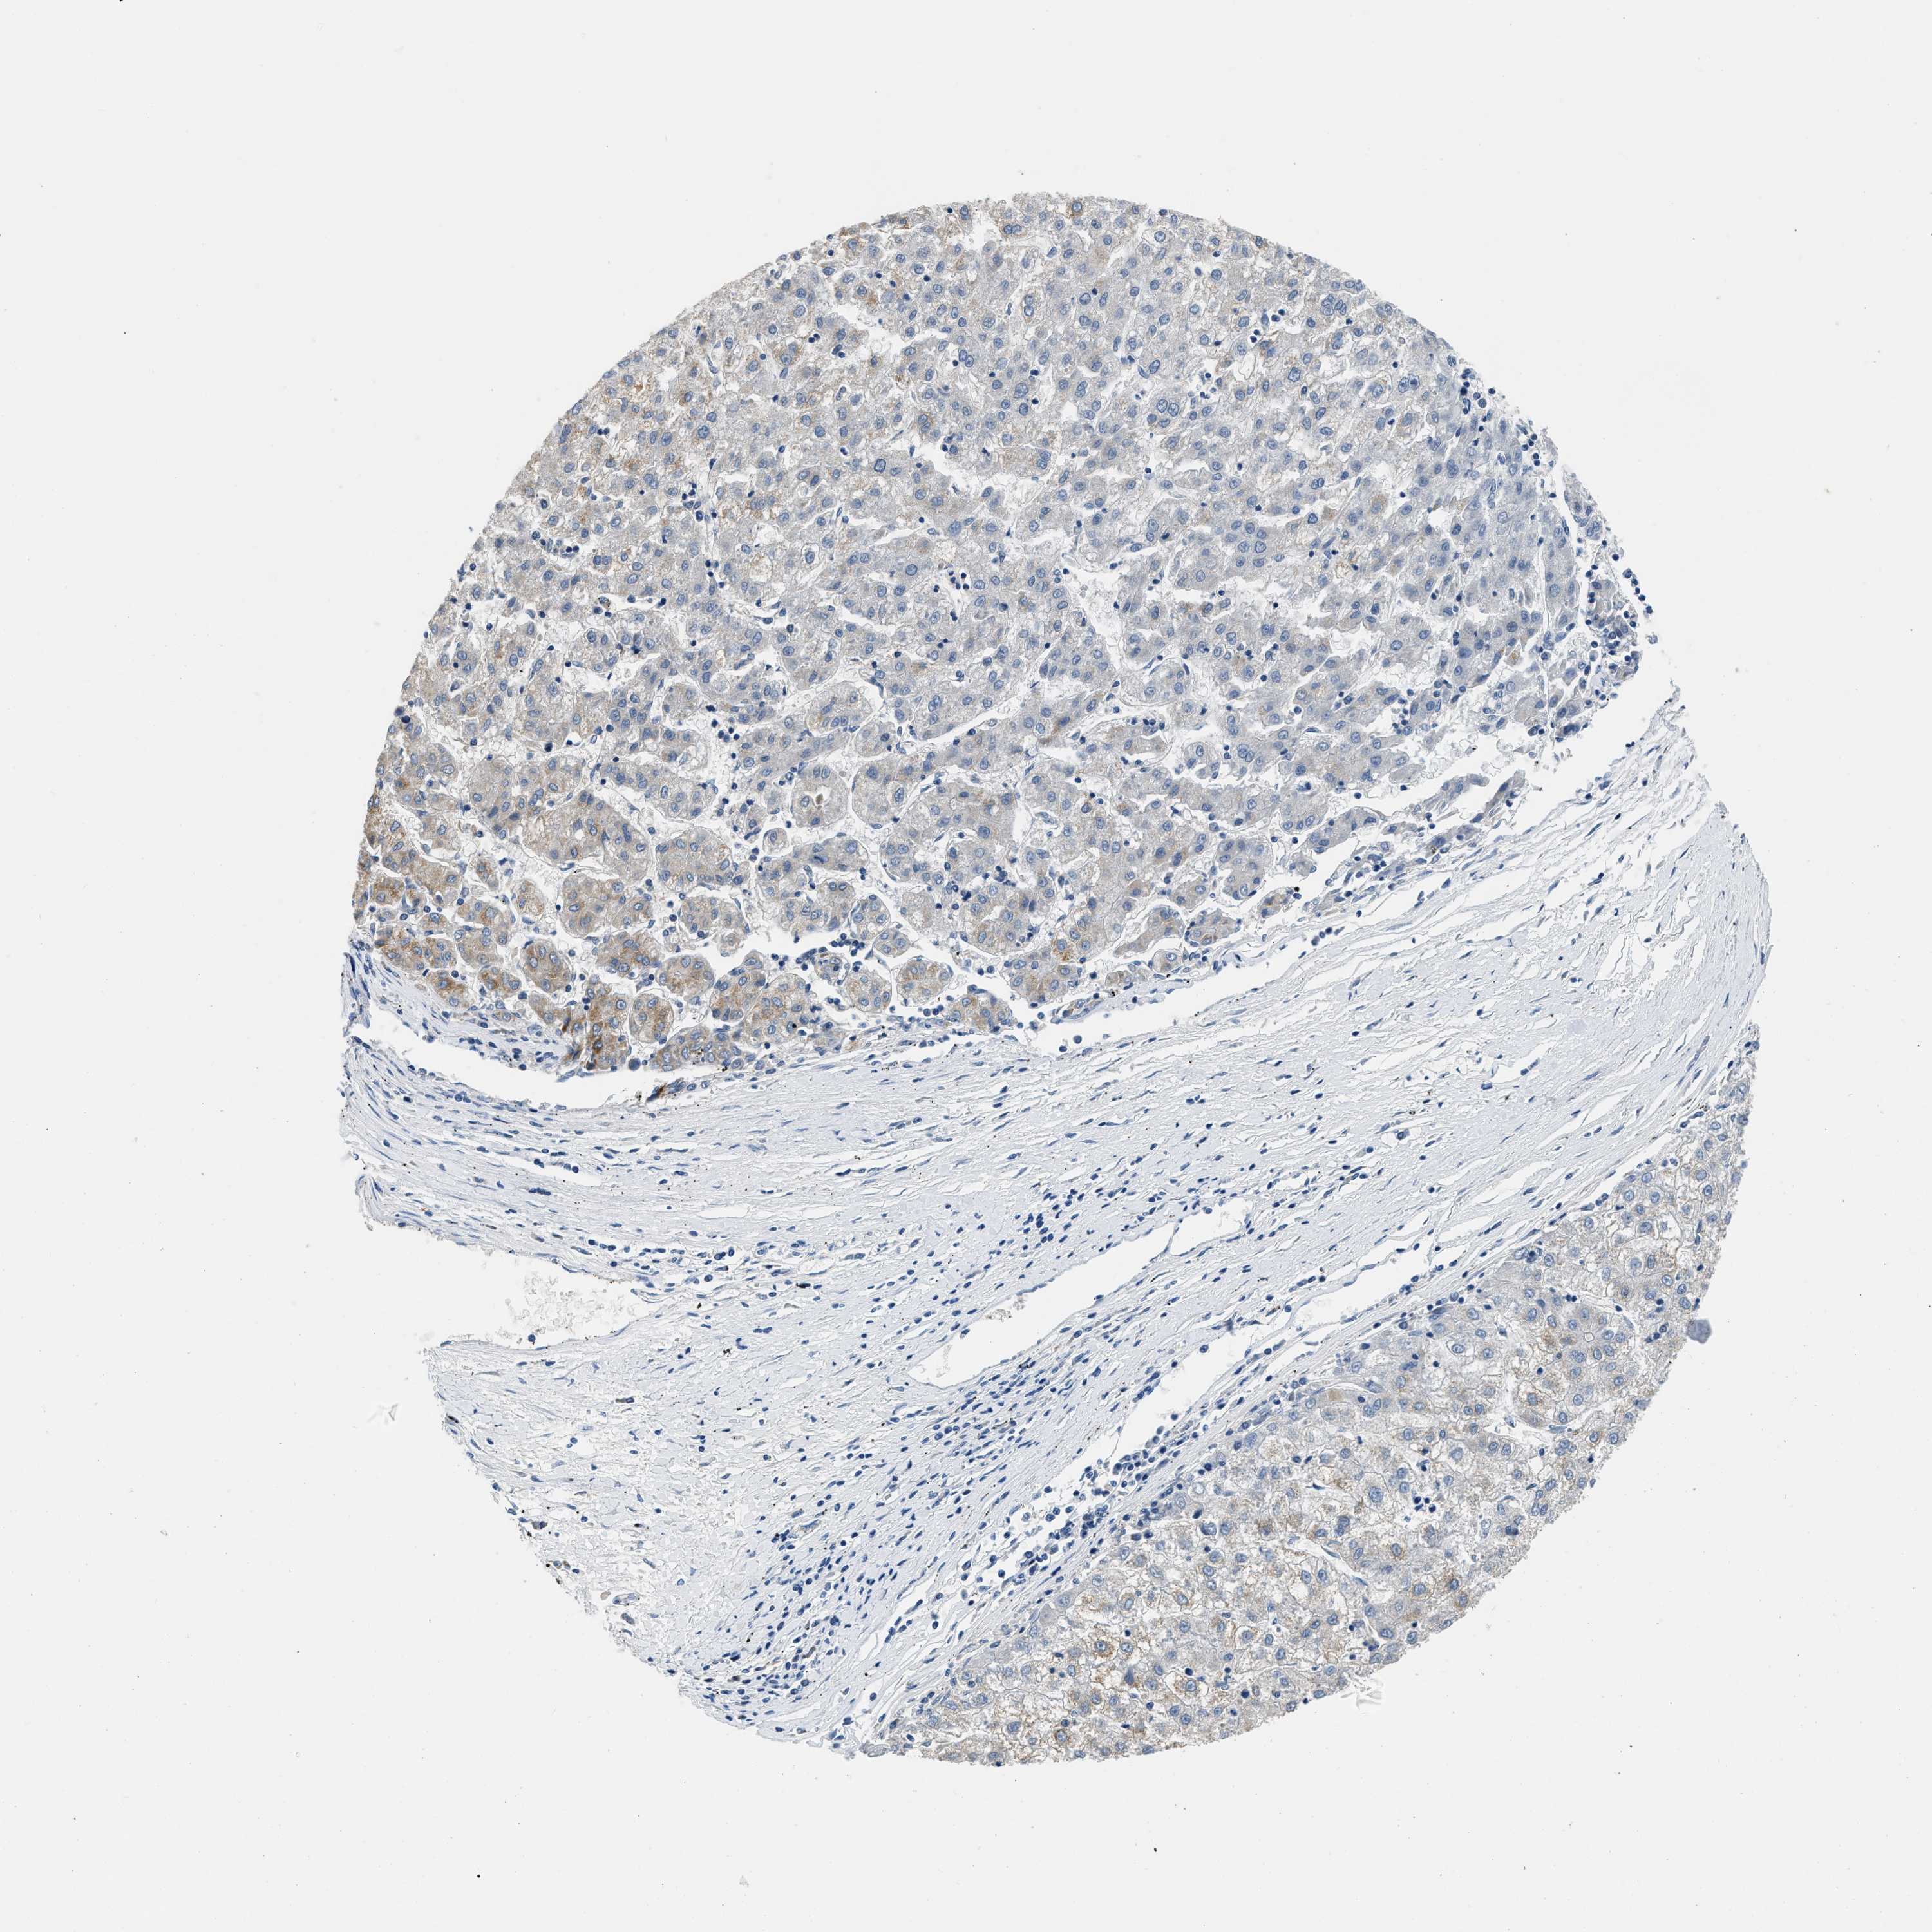

LIVER CANCER - Protein expressioni

A mouse-over function shows sample information and annotation data. Click on an image to view it in a full screen mode. Samples can be filtered based on level of antibody staining by selecting one or several of the following categories: high, medium, low and not detected. The assay and annotation is described here.

Note that samples used for immunohistochemistry by the Human Protein Atlas do not correspond to samples in the TCGA dataset.

Antibody stainingi

Antibody staining in the annotated cell types in the current human tissue is reported as not detected, low, medium, or high, based on conventional immunohistochemistry profiling in selected tissues. This score is based on the combination of the staining intensity and fraction of stained cells.

Each image is clickable and will lead to virtual microscopy that enables deeper exploration of all samples and also displays staining intensity scores, fraction scores and subcellular localization as well as patient and tissue information for each sample.

Antibody HPA051162

Antibody HPA053502

Antibody CAB018734

Staining

High

Medium

Low

Not detected

Intensity

Strong

Moderate

Weak

Negative

Quantity

>75%

75%-25%

<25%

None

Location

Nuclear

Cytoplasmic/membranous

Cytoplasmic/membranous,nuclear

Cholangiocarcinoma

Carcinoma, Hepatocellular, NOS